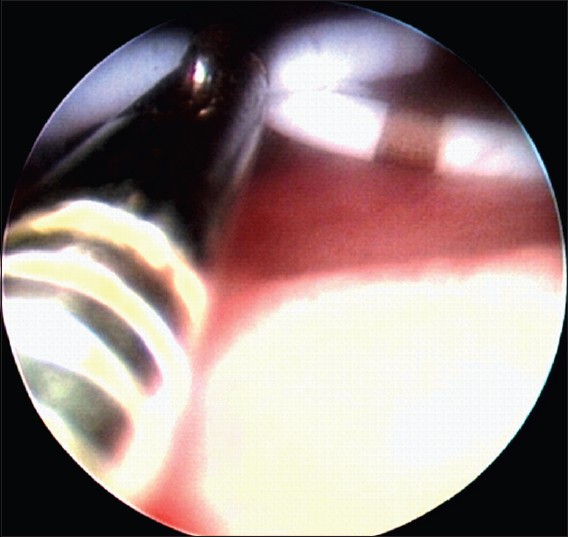

6 patients were subjected to bilateral DJ stent removal from February 2011 to November 2011 after written and informed consent. Indications for bilateral DJ stenting were following bilateral URS in 4 patients and bilateral extracorporeal shock wave lithotripsy for pelvic calculi in 2 patients. All patients were positioned in lithotomy. Rigid cystoscopy was done using 19 Fr Sheath and 30 degree lens (KARL STORZ, Germany) in all patients. 5 Fr stent removal forceps is passed through the channel of the cystoscope bridge into the bladder. The bladder is kept partially filled, otherwise the two crossing stents will diverge apart. The two stents appear to be crossing like a "X" when seen cystoscopically [Figure 1]. With the help of stent removal forceps, both the DJ stents are grasped at the point of crossing i.e. at the mid-point of "X" and retrieved simultaneously along with the cystoscope [Figure 2]. | Figure 2: Cystoscopic appearance of 5 Fr stent removal forceps grasping both the DJ stent at the mid point of "X" (or at point of crossing) and being retrieved